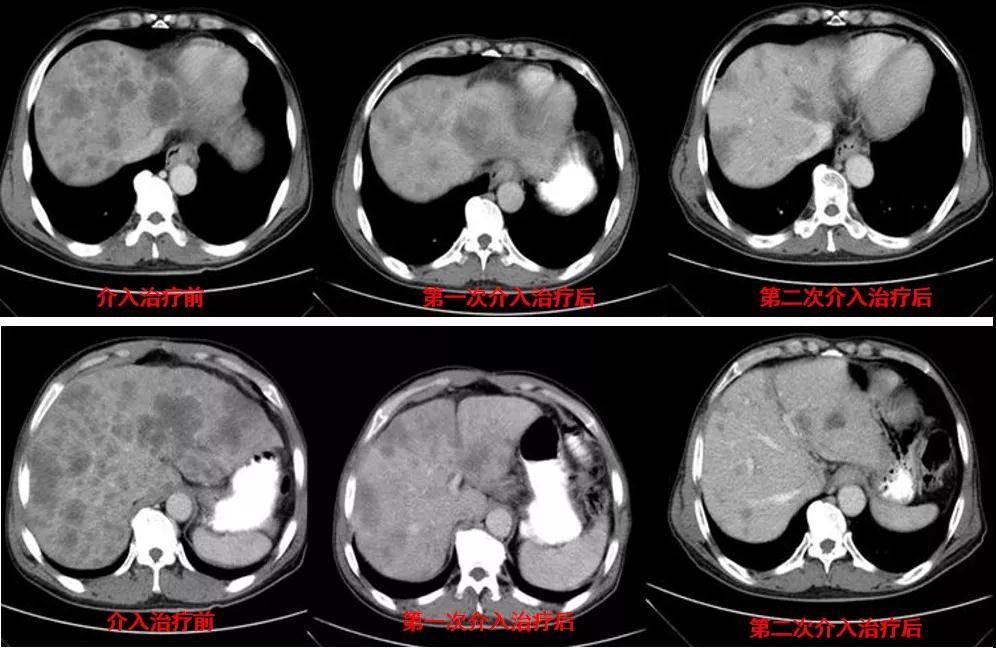

诊治经过:2020年12月16日患者行第二次经皮动脉化疗灌注栓塞术(铂类+氟尿嘧啶)治疗,并继续联合吡咯替尼治疗。结果见图3。

图3

讨论目的:第二次介入治疗后,患者肝转移病灶明显减少,针对少量肝转移病灶是否行射频消融治疗。

讨论:患者病灶进一步减小,病情控制好,治疗疗效显著且肝转移病灶大于3个,因此不建议行射频消融治疗,建议继续行介入联合靶向治疗。

诊治经过:2021年5月16日患者行第三次经皮动脉化疗灌注栓塞术(铂类+氟尿嘧啶)治疗,并继续联合吡咯替尼治疗。结果见图4。